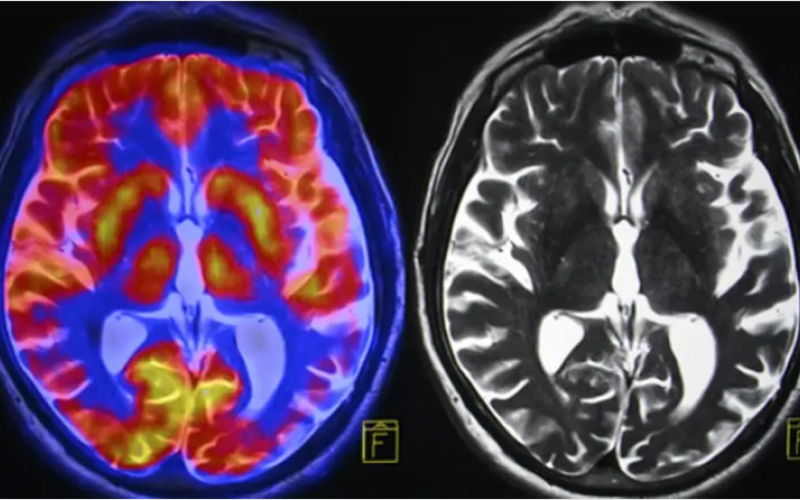

نيسان ـ يزعم باحثون في دراسة جديدة أنه أصبح بإمكان العلماء الآن تحديد سرعة شيخوخة الجسم بناءً على صورة واحدة للدماغ، وفقًا لما ورد في تقرير نشره موقع "Live Science" نقلًا عن دورية "Nature Aging".

طوّر فريق من الباحثين معيارًا للشيخوخة البيولوجية يعتمد على تصوير الدماغ بالرنين المغناطيسي. ويقول فريق الباحثين إن هذه الأداة قادرة على التنبؤ بمخاطر إصابة الفرد المستقبلية بضعف الإدراك والخرف والأمراض المزمنة، مثل أمراض القلب والضعف البدني والوفاة المبكرة.

لتطوير أداتهم، حلل الفريق صور الرنين المغناطيسي للدماغ المأخوذة من هذه المجموعة في سن 45 عامًا، وعالجوا البيانات المتعلقة ببنية الدماغ - حجم وسمك مناطق الدماغ المختلفة ونسبة المادة البيضاء إلى المادة الرمادية - من خلال خوارزمية تعلم آلي.

قارن الباحثون بيانات الدماغ المعالجة ببيانات أخرى جُمعت من المشاركين في الوقت نفسه، مثل اختبارات التدهور البدني والإدراكي والحالات الصحية الذاتية وعلامات شيخوخة الوجه، مثل التجاعيد. أكد الباحثون أن التراجعات الأكبر في تلك المناطق مرتبطة بوتيرة أسرع للشيخوخة بشكل عام، ثم ربطوا خصائص بيانات الدماغ بتلك المقاييس. أطلق الباحثون على نموذجهم الناتج اسم "سرعة دنيدن للشيخوخة المحسوبة من التصوير العصبي".